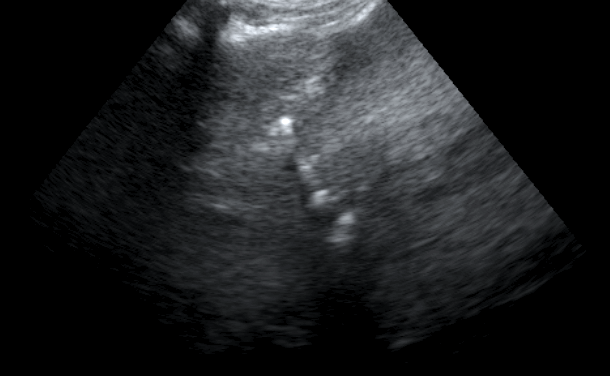

Findings: There was a loss of the normal sonographic appearance of the liver. There was also noted an increase in liver’s size. The owner did not want to proceed to an FNA or a Biopsy. During the evaluation of the portal vein, air was noted. There was also striation of the small intestine’s mucosa. The air must had travelled from the damaged intestinal mucosa through the cranial mesenteric vein, to the portal vein.

In these videos there is a dirty »shadow» caused by the air in the portal vein.